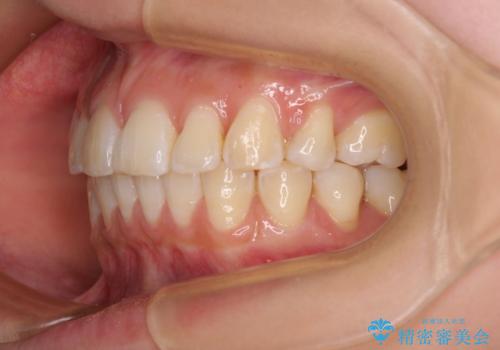

- 口を閉じたときに唇の間から飛び出してくる前歯を気にして来院された患者様です。

骨格的に上顎骨が前方位にあるため、左右の第一小臼歯を抜歯し、ワイヤー装置にて咬み合わせを整えていくこととしました。

前歯の突出感が改善されるだけでなく、奥歯の咬み合わせも改善され、食いしばりをしにくい状態に仕上げることができました。